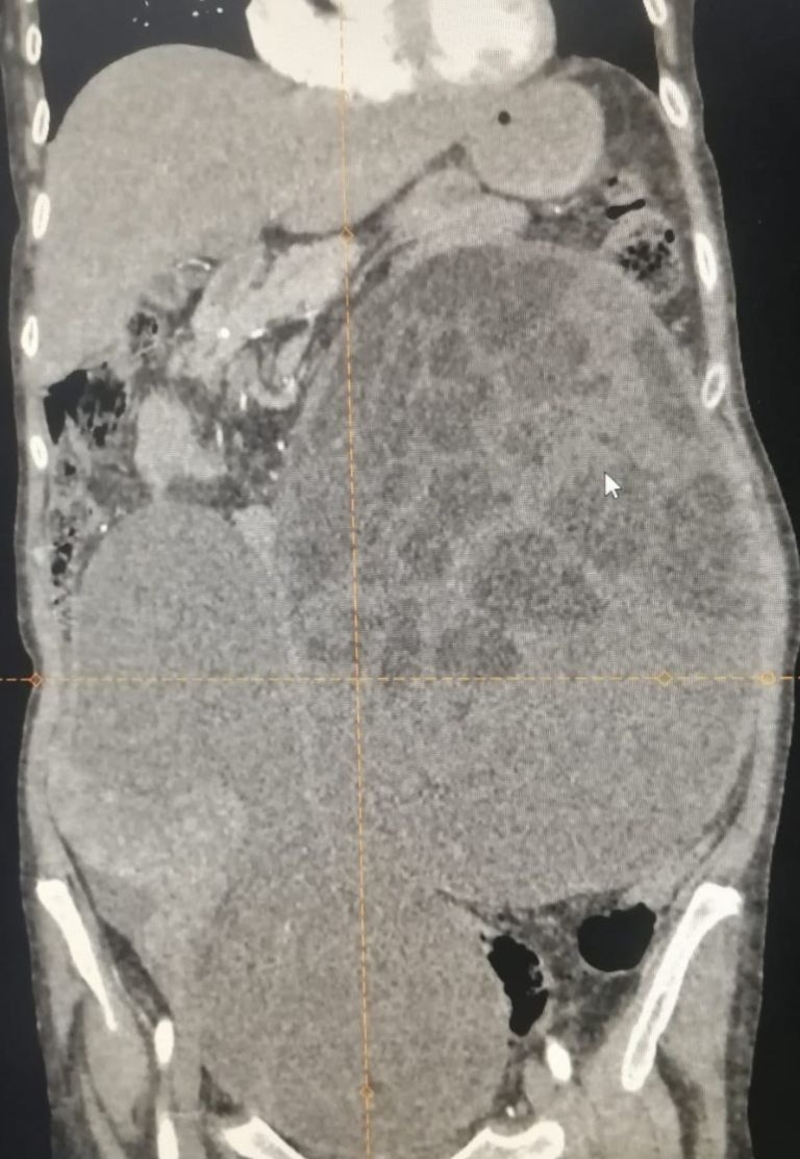

Врачи во время сканирования нашли опухоль, расположившуюся в брюшной полости и малом тазу. Специалисты выдвинули гипотезу, что она прогрессировала из правого яичника.

«Мы удалили из брюшной полости опухоль больших размеров — 27х21 см в диаметре, вес её составлял более 8 кг»,

— рассказал заместитель главврача Вадим Чугуевский.